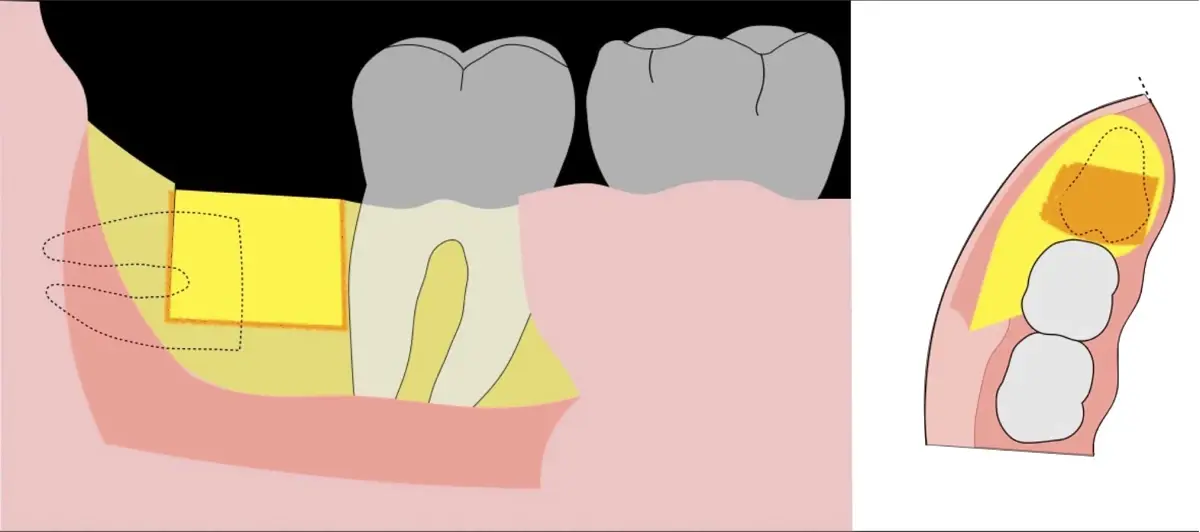

Figura 20. Retirada del segundo fragmento óseo (a). Ampliación de la ventana ósea con el inserto plano de corte de punta aserrada (b).

Figura 21. Ampliación de la ventana ósea con el inserto plano de corte de punta aserrada (a). Extirpación de tejido blando remanente con inserto de corte y coagulación del electro bisturí (b). Exposición de la corona clínica de la pieza 3.8 (c).

Figura 22. Ampliación de ventana ósea distal con inserto plano de corte de punta aserrada (a). Desplazamiento distal de pieza 38 con botador recto convencional (b).